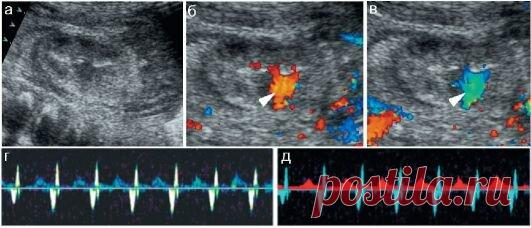

УЗИ почек и надпочечников, УЗИ надпочечников кисту почки (жидкостное образование), гидронефроз, мочекаменную болезнь, гиперплазию, гематому, опухоль (аденому или саркому), воспаление. общее состояние и внешний вид, внутренняя структура, функционирование.